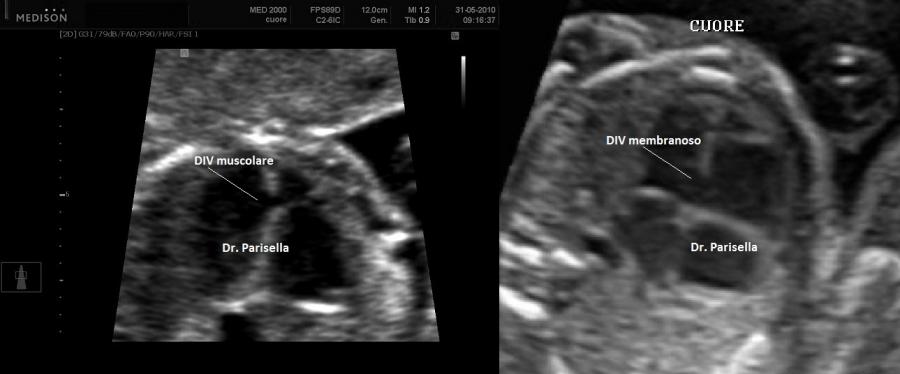

Le malformazioni cardiache più frequenti sono il difetto del setto interatriale tipo ostium secondum (DIA), il difetto del setto interventricolare (DIV) ed il DIA di tipo ostium primum.

• cardiopatie congenite (difetti settali)